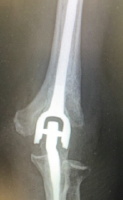

- Distal femoral anterior closing-wedge osteotomy (Fig. 3)

- Fixation of the osteotomy using 3.5 mm cancellous screws

- MPFL reconstruction (Fig. 4)

- Femoral fixation with screw.